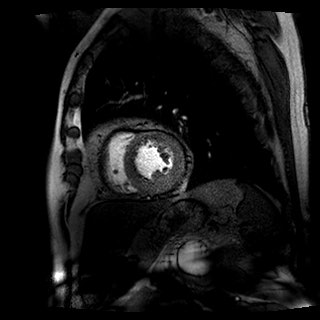

Coronary heart disease continues to be the leading cause of death and disability around the world, and MPI with SPECT is the most common test worldwide to assess myocardial ischemia. More recently, CMR has gained in popularity due to its noninvasive imaging approach and validated high diagnostic accuracy and prognostic results.

The 1,202 patients then were randomly categorized based on their treatment regimen. There were 240 subjects who followed U.K. National Institute for Health and Care Excellence (NICE) guidelines; 418 cases were directed by CMR results; and 481 individuals whose care was based on MPI findings. Efficacy of the three treatment strategies was determined on unnecessary coronary angiography result within 12 months.